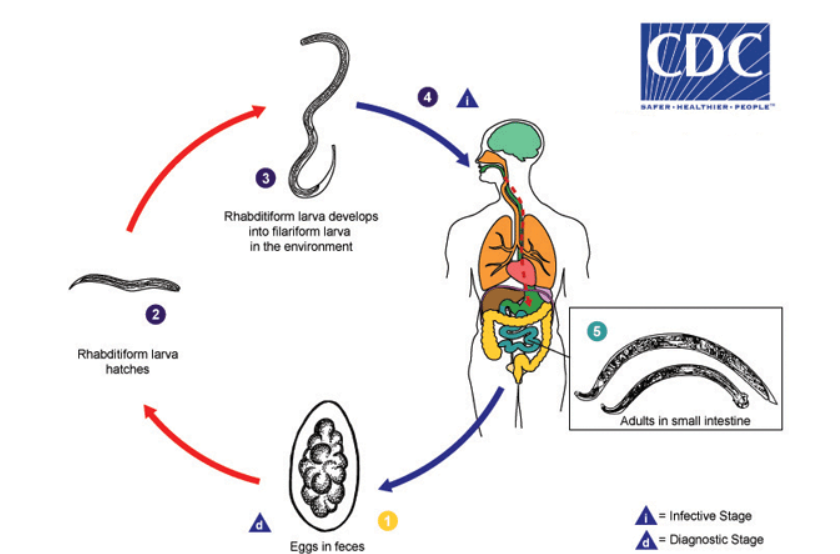

hookworm life cycle

unembryonated eggs are passed in feces

develop into rhabditiform larvae (1-2 days)

rhabditiform → filariform larva (lives 3-4 weeks in soil)

filariform penetrates skin of definitive host

larvae migrate to lungs; coughed up and swallowed

mature into adults in gut

adults live in small intestine